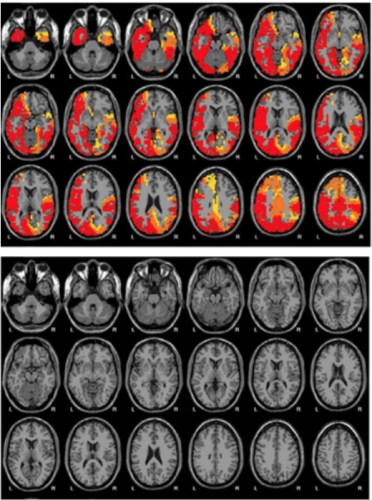

For an additional $400 fee, Emerald patients can have their brain scanned at a nearby clinic to document their progress with NAD therapy. An Emerald brochure shows a series of scans from a woman whose “brain is suffering from alcoholism.” Areas that glow red, orange and yellow — “HYPERACTIVE and OVERACTIVE” — totally disappear from the scans after 12 days of NAD therapy, according to the company.

“This is totally bogus,” says Leslie Hulvershorn, an addiction psychiatrist at the Indiana University School of Medicine with expertise in brain imaging who reviewed the images via email. “We do not have research in our field that allows us to use EEG or any other brain imaging technique to document treatment response.”